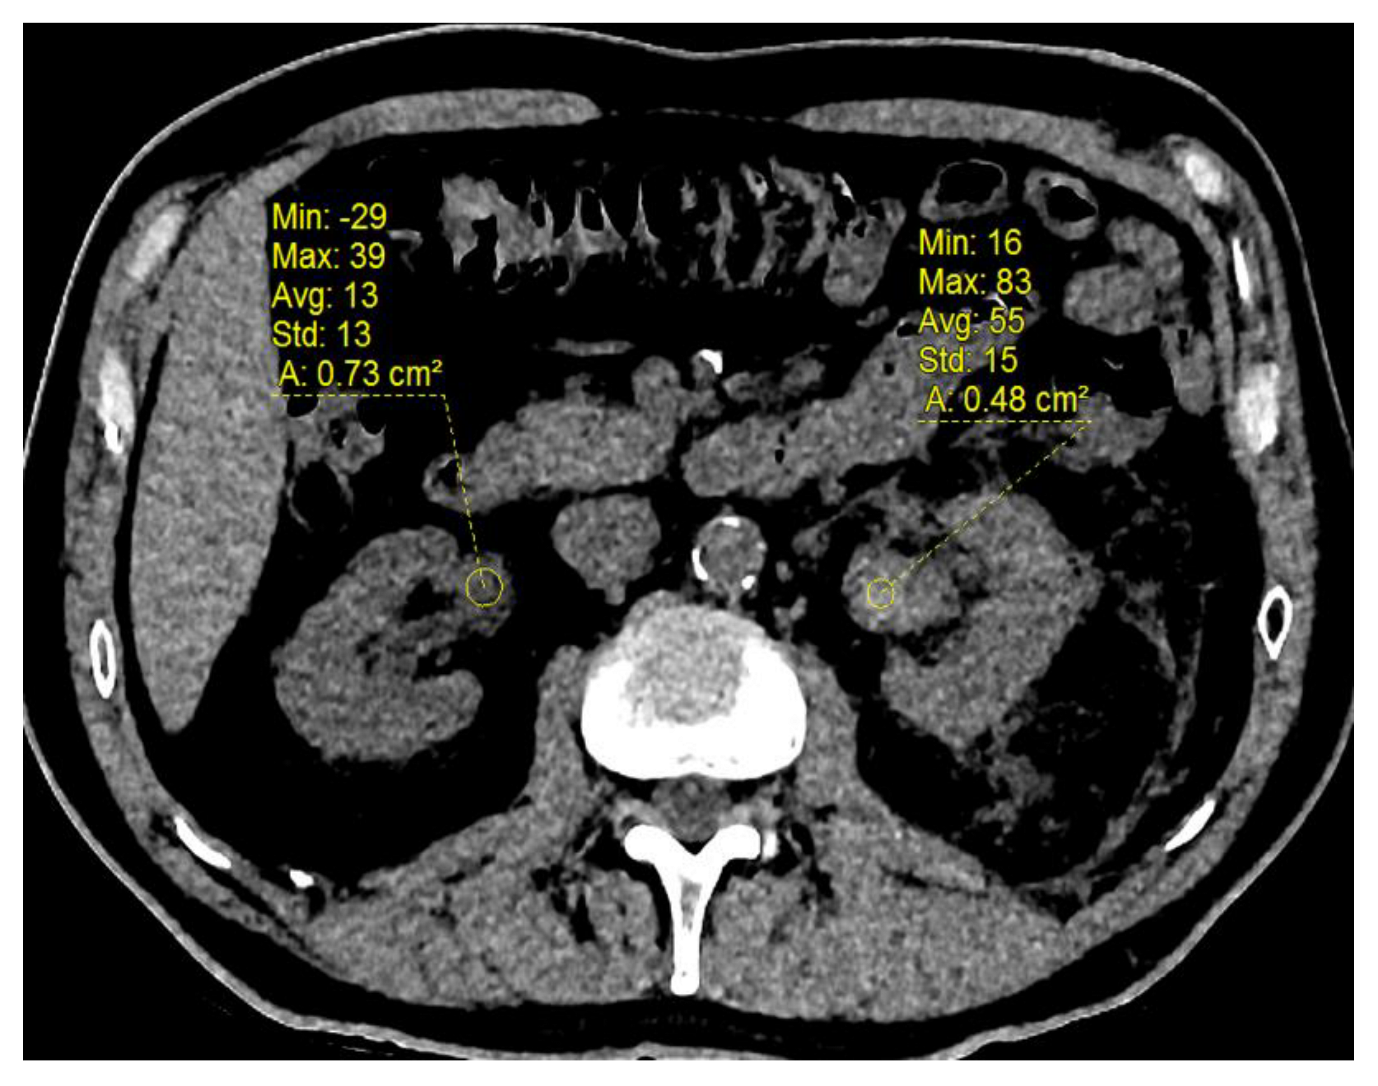

2.4. Computed Tomography (CT) Acquisition

3.4. Change in Renal Functional Volume

| Aneurysm size (mm) | 10.5 (±4.7) |